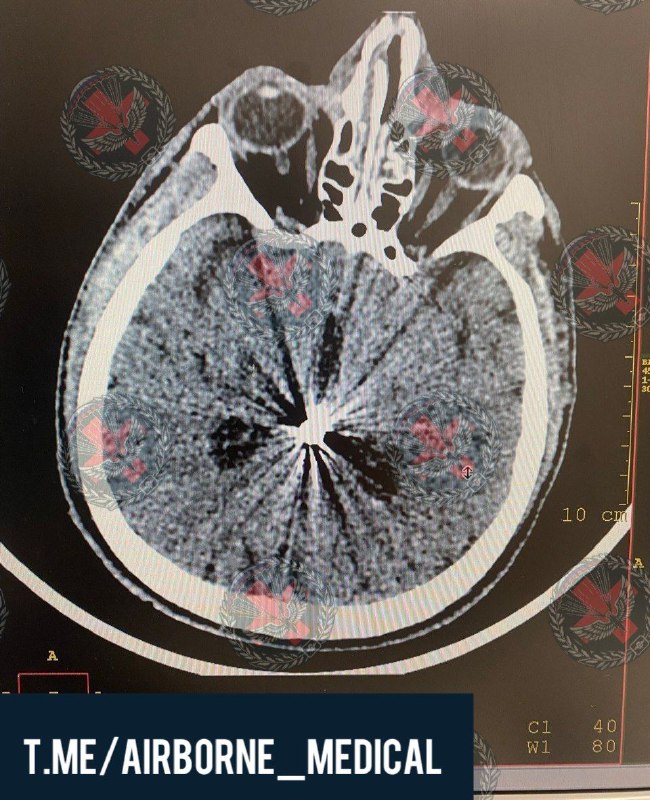

Эпидуральная гематома — это опасное состояние, которое может возникнуть при травмах головы, особенно в условиях современных военных конфликтов. В условиях боевых действий увеличивается риск тяжелых травм черепа и сосудов, что способствует развитию этого вида гематомы. Чаще всего она встречается у военнослужащих и гражданских лиц, получивших сильные удары по голове.

Особенность эпидуральной гематомы — быстрое развитие симптомов и риск серьезных осложнений, таких как сдавление мозга и смерть. Поэтому очень важно оказать своевременную медицинскую помощь. Быстрая диагностика и хирургическое удаление гематомы могут спасти жизнь и предотвратить инвалидность. В условиях боевых действий особенно ценна быстрая эвакуация пострадавших в специализированные медицинские учреждения для получения необходимого лечения.